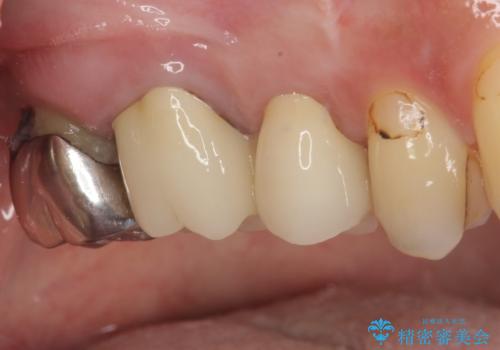

目立つ銀歯も根管治療を行い、その後2本の歯をオールセラミッククラウンにて補綴治療を行うこととしました。

大臼歯では、根管治療後にも痛みが残ってしまったため、外科的歯内療法(歯根端切除術)を適用しました。外科処置直後は腫れや痛みなどがありましたが、半年が経過し、痛みがなくなり、レントゲン写真上でも炎症の消退が認められました。